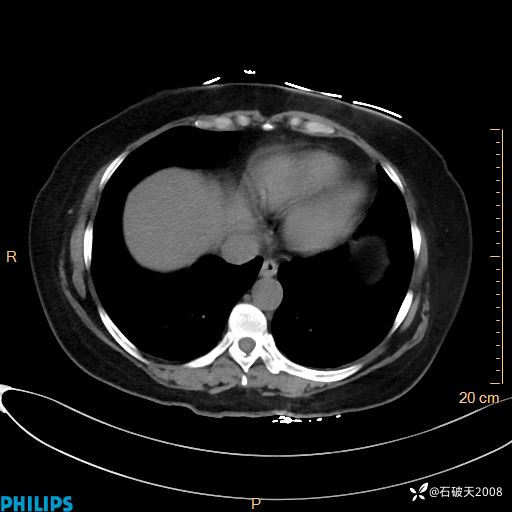

肺结节病?纵膈型肺癌?淋巴瘤?有点意思,欢迎围观

女 52岁 主 诉:咳嗽10余天,咳痰2天。

现病史:10余天前无明显诱因出现咳嗽,呈阵发性干咳,伴咽喉部发痒,无咽痛,无咳痰,无鼻塞、流涕、打喷嚏,无发热、畏寒、寒颤,无头痛、头晕,无胸闷、胸痛,无反酸、烧心,无腹痛、腹泻,无尿频、尿急,无皮疹等,在当地诊所求治,给予口服药物治疗(具体不详),病情无好转。遂在当地社区卫生服务中心开具口服药物治疗(具体不详),疗效欠佳。2天前出现咳痰,在我院门诊求治,行胸部CT提示肺部感染,建议住院,患者要求口服药物治疗,目前仍咳嗽、咳白色粘痰,白天量多,夜间自觉喉部喘鸣音,遂再次来院就诊,以“肺部感染”为诊断收入院。发病以来,神志清,精神可,饮食可,夜间睡眠差,大小便正常,近期体重无明显变化。

肺窗